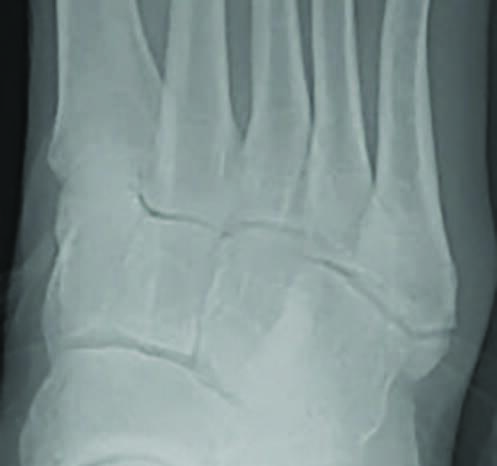

Lawrence and Dameron Zone 3 fractures are typically considered stress fractures and occur in the proximal diaphysis of the distal to the fourth and fifth intermetatarsal joint (see third photo above).